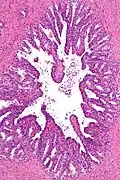

Microanatomía

El revestimiento interno de las vesículas seminales (el epitelio) está formado por un revestimiento de células intercaladas en forma de columna y de cubo.[7] Existen diversas descripciones del revestimiento como pseudoestratificado y formado únicamente por células en forma de columna.[8] Cuando se observan al microscopio, se ve que las células tienen grandes burbujas en su interior. Esto se debe a que su interior, llamado citoplasma, contiene gotitas de lípidos que intervienen en la secreción durante la eyaculación.[7] El tejido de las vesículas seminales está lleno de glándulas, espaciadas irregularmente.[7] Además de glándulas, las vesículas seminales contienen músculo liso y tejido conjuntivo.[7] Este tejido fibroso y muscular rodea las glándulas, ayudando a expulsar su contenido.[3] La superficie externa de las glándulas está cubierta de peritoneo.[3]

Micrografía a bajo aumento de la vesícula seminal. Tinción de H&E. -

Micrografía a gran aumento de la vesícula seminal. Tinción H&E.